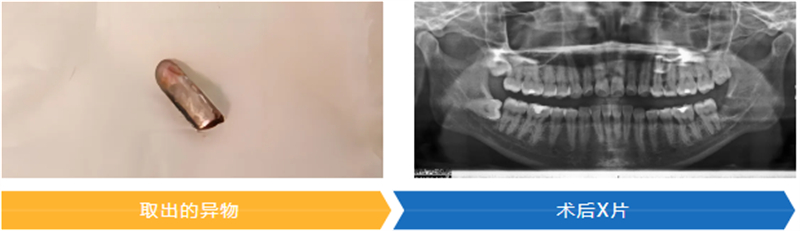

最終,團隊憑借豐富的臨床經驗和默契配合,成功將一枚拔牙挺的斷端取出。術后患者生命體征平穩,疼痛癥狀明顯緩解,經影像檢查確認異物完整取出,目前已進入康復觀察階段。